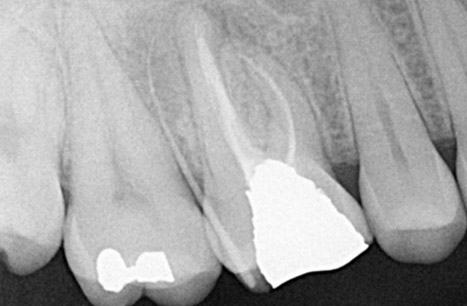

Endodontics is the study and treatment of disorders of the neurovascular tissue within the interior of teeth, including the pulp chamber and roots. These disorders occur most often when the root canal becomes infected as a result of extension of dental caries into the pulp chamber. With infection of the neurovascular tissue, necrosis can occur, and the disease process can progress to involve the entire root canal system (Figure 1). Pain, often intense, will be experienced by the affected individual. As necrotic debris becomes located at the apex of the root in the alveolar bone, the infection can extend beyond the local area to include the more coronal periodontal tissues (Figure 2). Obvious clinical swelling and suppuration can be present. The bacteria that characterize these acute lesions are Gram-negative anaerobes. These infections can be associated with systemic symptoms, including fever and malaise.

Figure 2. Radiograph of a maxillary first molar demonstrating a combined endodontic-periodontal lesion. Following endodontic treatment, there is widening of the apical area of the palatal root. A gutta-percha point introduced into the gingival sulcus from the buccal surface extends to the root apex. Radiograph courtesy of Drs. Y. Berlin-Brenner and L. Levin.

- Figure 2